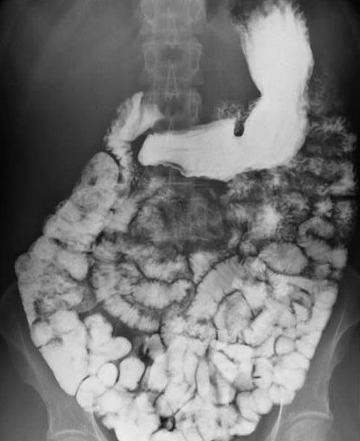

위조영술 검사는 바륨이라는 하얀 액체를 마시고 그 액체가 식도를 타고 내려가면서 위에 쌓였을 때 몸을 이리저리 뒤집어가면서 그 흑백화면을 보면서 읽어내는 검사방법입니다.

바륨현탁액, 요오드제제를 이용해 위의 이상 유무를 검사합니다. 이 용액은 X선 투과가 잘 안되는 물질로 이 용액을 마시고 X선이 발생되는 기계 위에서 몸을 이리저리 돌려가면서 검사를 받습니다. 기계가 알아서 돌아가는 것이 아니라 사람이 직접 그 기계 위해서 몸을 움직여 줘야 합니다.

X선이 발생하는 기계 위에 있으므로 그 방사선이 몸을 투과하므로 미량의 방사선 피폭이 있다는 것은 인지해야 합니다. 위조영술 검사방법은 위를 풍선처럼 팽창시켜 위벽에 조영제 코팅해 위벽 병변 유무를 검사하는 방법과 위가 팽창하지 않은 상태에서 위를 조영제로 채워 검사하는 두가지 방법이 있으며 일반적으로 두가지 다 시행해야 위벽과 안을 다 검사 할 수 있습니다.

하지만 위조영술 검사 장점도 분명히 존재합니다. 이는 그래도 위내시경 검사처럼 굵은 카메라를 삼켜야 하는 불편함이 없으며 노인이나 기저질환이 있는 환자도 위 검사를 받을 수 있고 식도에서 위 그리고 십이지장으로 이어지는 위장관의 전체적 모양과 연동운동을 관찰 할 수 있다는 점입니다.